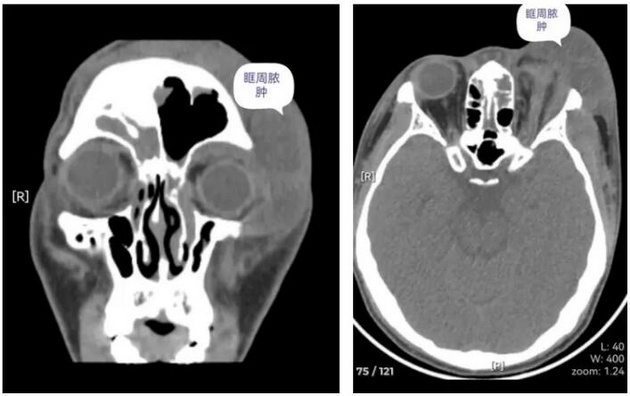

周彬教授在门诊详细询问南南发病经过并行鼻窦CT检查,发现南南的“肿眼泡”很可能是感冒后急性鼻窦炎引起的眶周及眶内感染。为其办理入院后进一步行眼眶磁共振检查,明确额部及左眼眶脓腔部位,予以穿刺抽出脓液超过40ml,南南眼球“胀”出来的感觉减轻了许多。

经过周密的术前准备,周彬教授为南南施行鼻内镜下左侧额窦及筛窦开放术,术中见大量脓液经额筛窦口引出,全麻清醒回病房后家属发现南南的“肿眼泡”不见了,眼睛也能睁开了,整个病房都跟着开心,没想到手术效果这么快这么好,原打算要经眉弓的切口也不用切了。